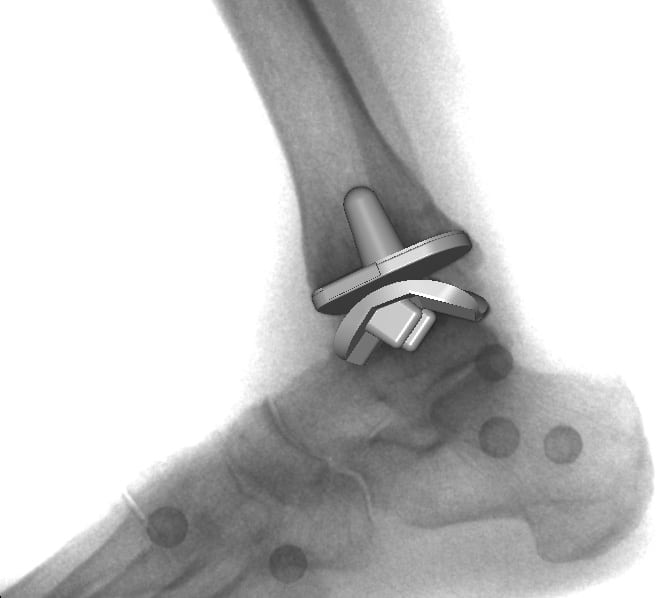

Сложность их конструкции обусловлена анатомическим строением голеностопного сустава, разнообразием осуществляемых функций. При создании всех моделей учитывались статико-динамические нагрузки, составляющие 3-13% массы тела. При конструировании тотальных имплантатов используются следующие элементы:

- округленные металлические пластины, защищающие поверхность таранной кости;

- металлические пластины для закрытия части большой берцовой кости;

- подвижное ядро из высокомолекулярного полиэтилена.

Такой способ хирургического вмешательства считается щадящим, так как сохраняется значительное количество суставных структур. Ранее при проведении операции могли использоваться длинные стержни. Теперь крепление пластин таранной кости осуществляется штифтами для плотного анатомического облегания костных поверхностей имплантационным покрытием. При его изготовлении применяется особый пористый материал, способствующий прорастанию сосудов и тканей. Это обеспечивает естественную и прочную фиксацию пластины. Короткий дюбель используется для крепления нижней защитной пластины, а вот ядро не закрепляется вовсе. Оно предназначено для обеспечения плавного скольжения между верхней и нижней металлическими пластинами. Верхний элемент имеет ограничитель, предупреждающий смещение ядра.

Установленный искусственный протез имеет те же функциональные характеристики, что и голеностопное сочленение. При его вживлении хирурги используют программное обеспечение для контроля баланса и фиксации имплантата. Это способствует длительному сроку службы протеза и отсутствию дискомфортных ощущений во время эксплуатации. Объем движений полностью восстанавливается, а за счет полимерных элементов в конструкции снижается трение, компенсируется нагрузка при соприкосновении собственных костных тканей пациента с имплантатом.